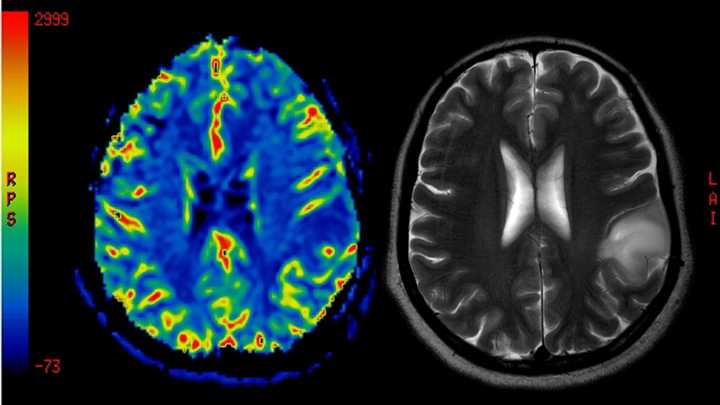

Imagen de archivo de una resonancia magnética. iStock

Hasta el momento, el cerebro era un órgano del que todavía quedaba mucha información por descifrar. La gran asignatura siguen siendo las enfermedades mentales, por qué se producen y cómo curarlas. Ahora, la ciencia está un pasito más cerca. Un consorcio internacional de investigadores ha publicado este miércoles los mapas más detallados hasta el momento del desarrollo del cerebro en mamíferos , donde se incluye, también a humanos.